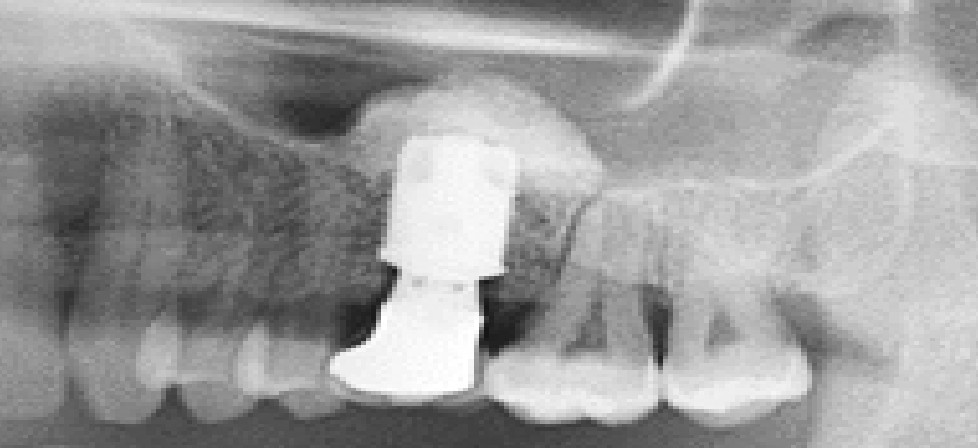

Osteoprzewodzący charakter powierzchni Ti-oss® oceniono na podstawie próbek biopsyjnych.

Konsekwentne tworzenie się nowej tkanki odnotowano w kilku różnych przypadkach klinicznych, dzięki czemu jesteśmy w stanie osiągnąć, przewidywalność i niezawodność procesu regeneracji we wczesnych etapach tworzenie się nowych struktur.

Research Report date: May, 2012 • Kim, Sun Young, D.D.S. Prosthodontist • Suplant Dental ClinicSeoul, Korea

Wyniki biopsji po 3 miesiącach

Wyniki biopsji po 4 miesiącach